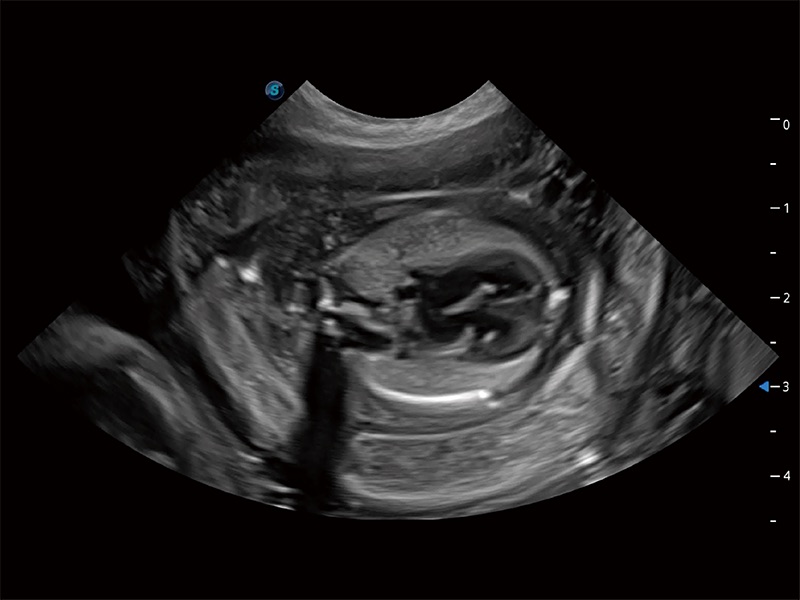

優(yōu)異的基礎(chǔ)圖像

ProPet 80 全新的動物超聲智能軟件和豐富的探頭群,為動物醫(yī)生提供了高清晰度和精細(xì)分辨率的圖像,無論在寵物、馬科、畜牧還是實驗室動物等應(yīng)用中都可以輕松應(yīng)對,為您的日常工作帶來滿意的體驗。

(犬)胎兒四腔心